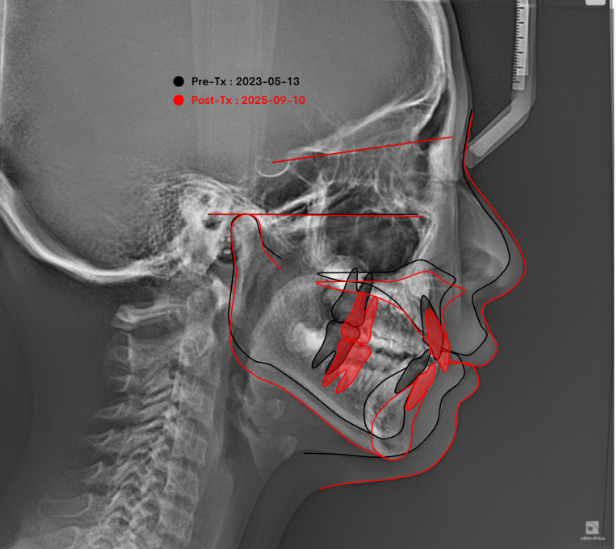

23.06~25.06

2년간의 골격 변화를 중첩해보겠습니다

아래턱이 많이 자라나왔는데 하관 길어짐 없이 바람직한 성장이 일어났습니다.